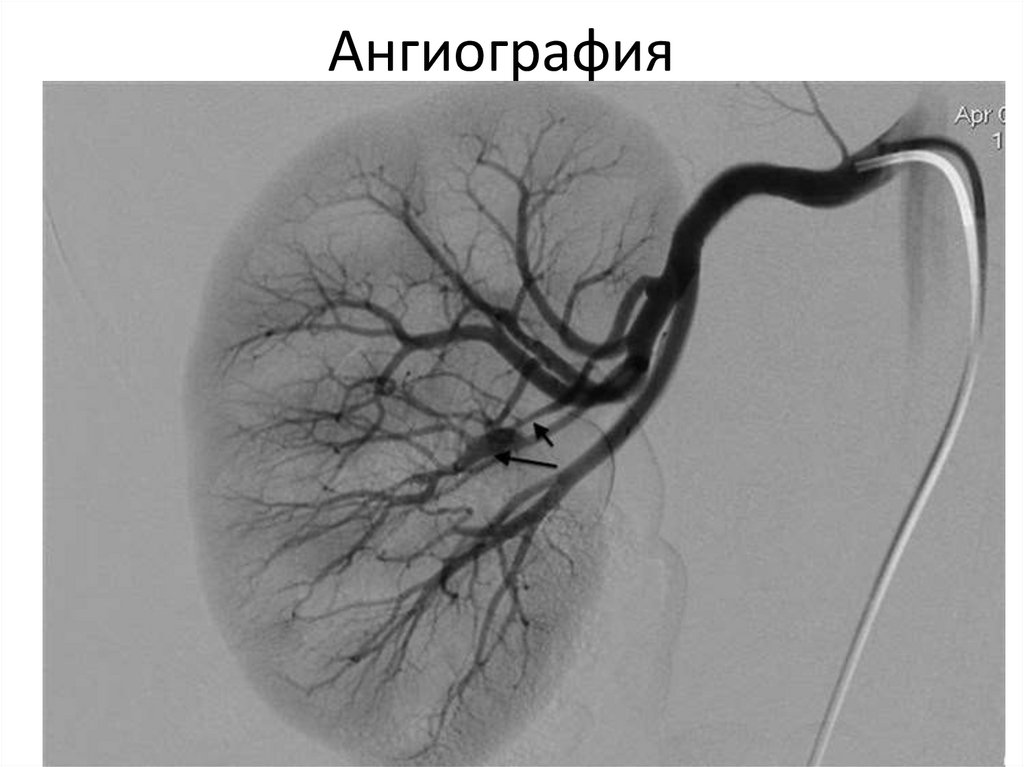

Ангиография

11.